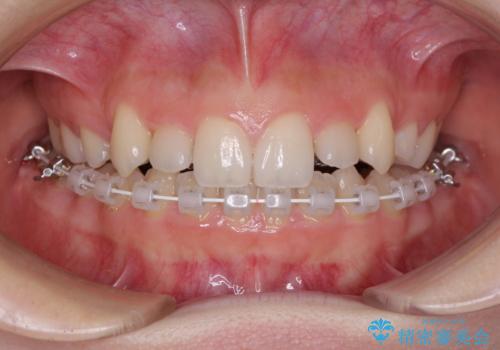

目立つ八重歯を目立たない装置で ハーフリンガルによる抜歯矯正

- ハーフリンガル

- 前歯のデコボコと八重歯を気にして来院された患者様です。

目立たない装置を希望されたので、上顎が裏側装置のハーフリンガルを選択し、左右上顎小臼歯1本ずつを抜歯して、矯正治療を行うこととしました。

治療期間の目安は2年半~3年間でしたが、予定通り治療が進み、2年半弱で終えることができました。

歯列はきれいに整い、治療期間も予定通りであり、患者様には大変満足していただきました。